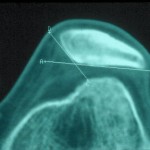

El TAC o escáner sirve para estudiar en profundidad el caso, como este que se muestra a la derecha donde se ve perfectamente la basculación de la rótula con desplazamiento externo, con lo que se encuentra subluxada o fuera del canal troclear.